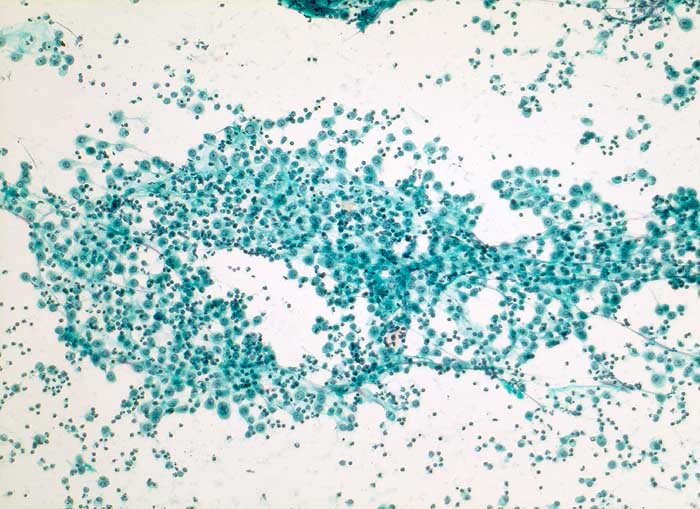

pit/ Reaktiv veränderte Mesothelzellen

Reaktiv veränderte Mesothelzellen

Irritierte Mesothelzellen beginnen zu proliferieren. Die Zellen werden plump und kubisch, die Kerne sind vergrössert. Diese reaktiven Mesothelien können mit Karzinomzellen verwechselt werden. Mesothelzellen können Tumoren imitieren, indem sie kleine Gruppen, Pseudoverbände, Zellballen, Pseudopapillen, "cell in cell" und "Indian files" ausbilden. Unter reaktiven Bedingungen kommen sehr grosse und mehrkernige Mesothelzellen vor. In Zweifelsfällen empfiehlt sich eine immunzytochemische Untersuchung mit Calretinin (Mesothelien positiv) und BerEP4 (Karzinomzellen positiv).